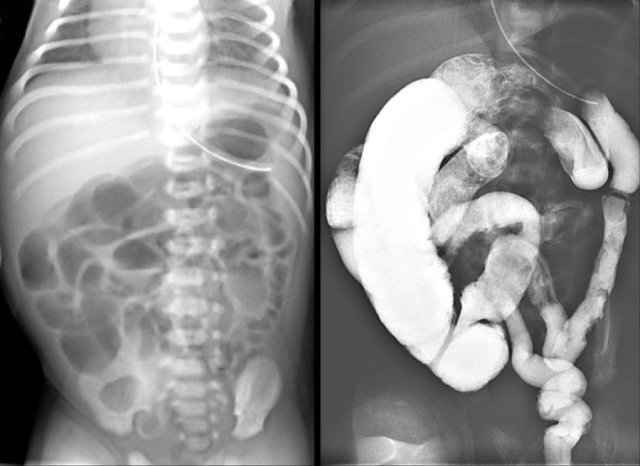

2. Number of dilated loops?

Up til three dilated small bowel loops on an abdominal radiograph generally indicate a high obstruction.

The left image shows a case of jejunal atresia.

More than three dilated loops indicate a low obstruction.

The image on the right is a case of ileal atresia.